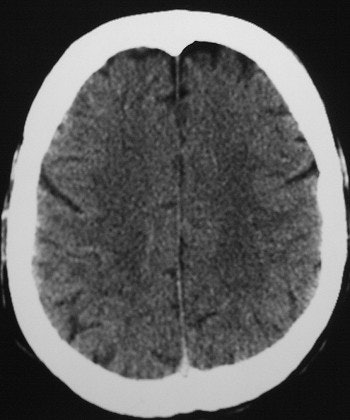

Axial cuts at the levels of the lateral ventricles and centrum semiovale (mAs 335, kv 120). A loss of GWMD is shown in a 51-year-old comatose patient with exertional HS in comparison to good GWMD in a 50-year-old patient, below. Images courtesy of Dr. Oded Szold.

According to the results, "all six patients demonstrated severe loss (grade 2-3) of the GWMD. None suffered from CNS bleed or displacement of anatomical structures. The difference on CT between the gray and the white matter is thought to be due to the higher content of water and lower content of lipids in the gray matter. This results in higher oxygen and lower carbon concentrations in the gray matter, causing increased photoelectric absorption," they said.